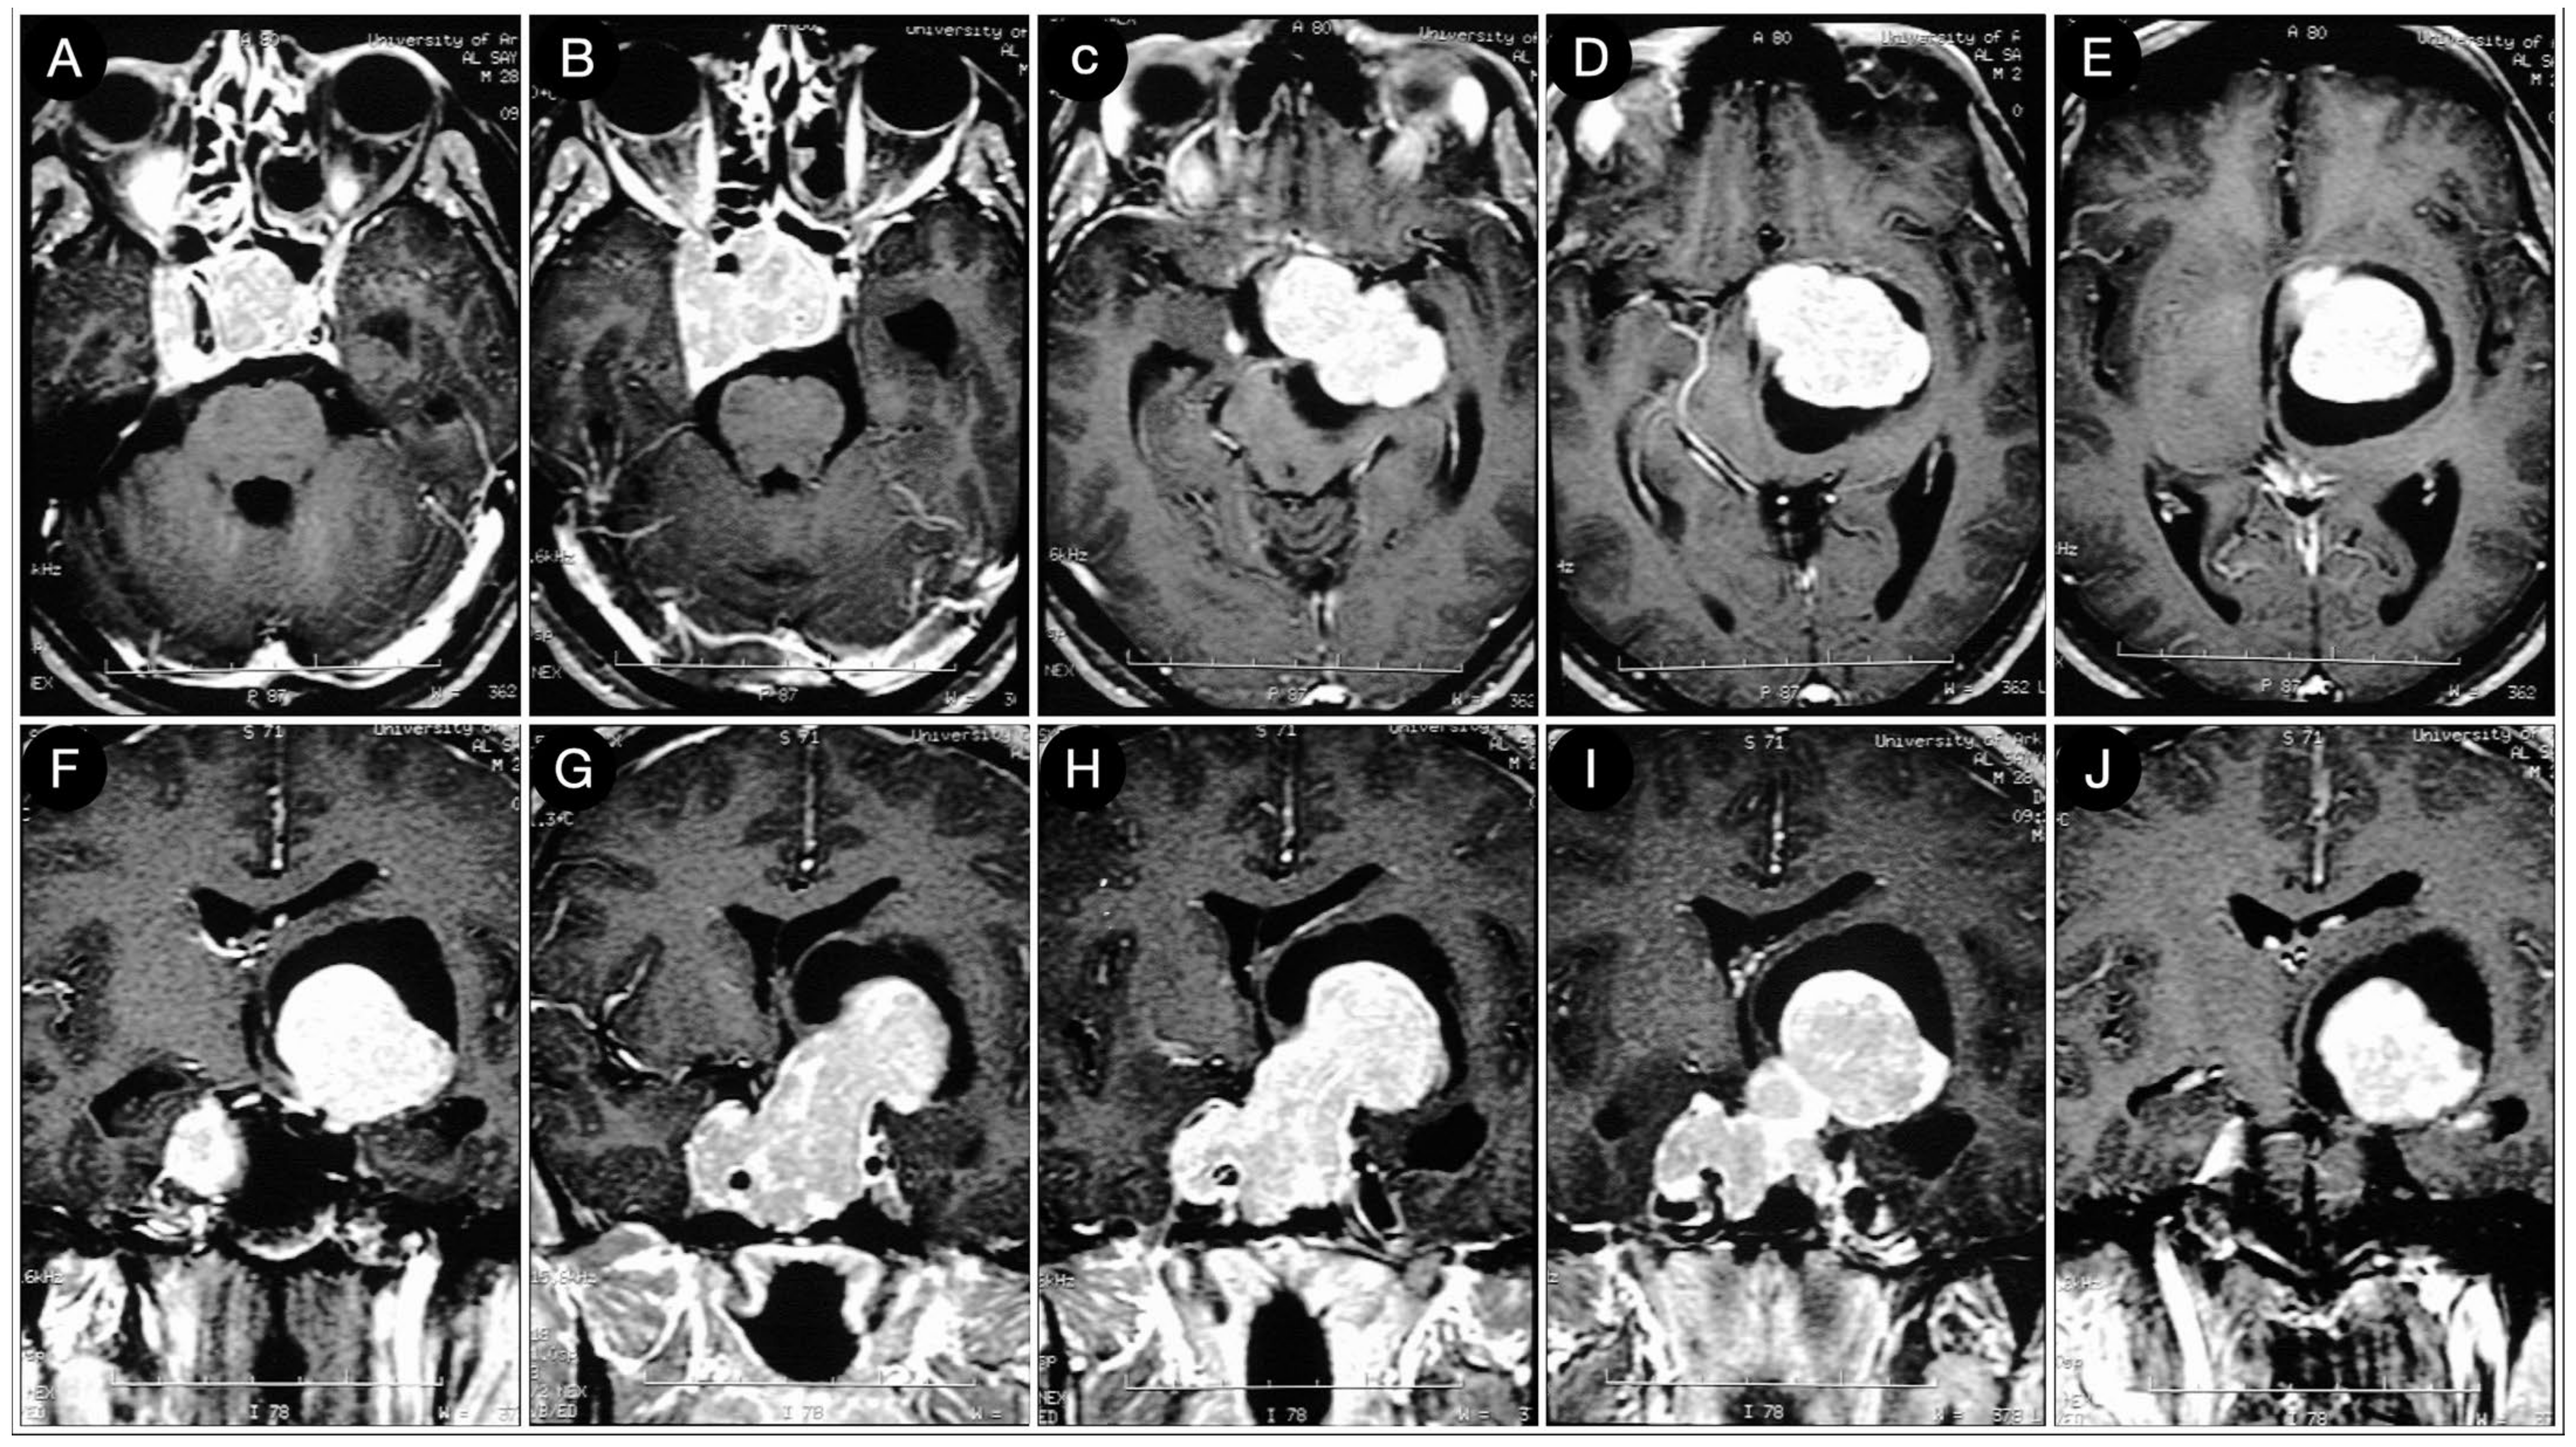

Case #1: Infradiaphragmantic Tumor with Middle Fossa Involvement through the Cavernous Sinus

3.3.2. Case #5: Extension beyond the Lateral Wall of the Cavernous Sinus

3.3.3. Case #6: Encasement of the Posterior Communicating and Anterior Choroidal Artery

Case #7: Encasement of the Paraclinoid and Supraclinoid Internal Carotid Artery